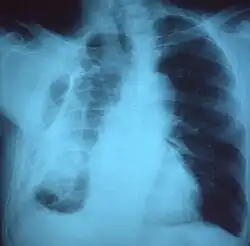

Fibrotórax extenso en el lado izquierdo. -

Radiografía de tórax que muestra opacidad heterogénea en la mitad izquierda del tórax por fibrotórax. -